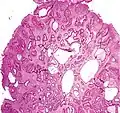

| Hyperplastic polyp | Colorectal (unless otherwise specified) | Serrated unbranched crypts | if polyps are more than 100 | ![]() |

Serrated polyposis syndrome |